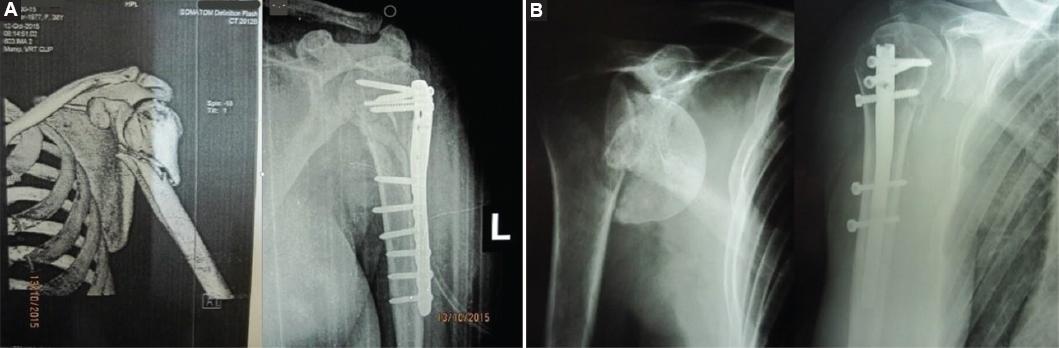

Osteosynthesis of the fracture was achieved using plate and screws or intramedullary locking nail (Fig. 1). Surgery was performed on the radiolucent table with the patient in the "beach chair" position. Deltopectoral approach was utilized for plating of the fractures, whereas the nailing was performed and managed through a minimally invasive anterolateral technique (deltoid splitting approach). During surgery, the position of fragments was verified with C-arm. Regardless of the type of osteosynthesis, post-operative Desault immobilization was indicated for a period of 4-6 weeks, with the upper arm in 45° of abduction, elbow in 90° of flexion, and neutral rotation of the forearm. The duration of immobilization depends on the fracture pattern, the patient´s age, the quality of reduction, and the fixation strength. For the first 48 h, parenteral antibiotic prophylaxis, which included first-generation cephalosporins, was administered. Post-operative X-rays were made 10 days, after the surgery, after 3 and 6 weeks, 3 and 6 months postoperatively. The mean follow-up time was 4 years (1-9 years). All patients were operated on by the same surgeon.